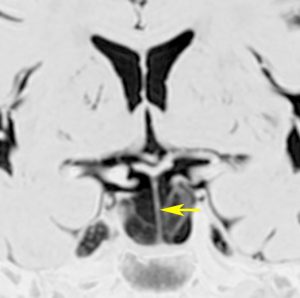

これは11歳の子供で偶然発見された右側脳室くも膜のう胞です。無症状で変化しませんからほっておきます。右のモンロー孔に狭窄があるために右側脳室だけの停止性水頭症になっています。